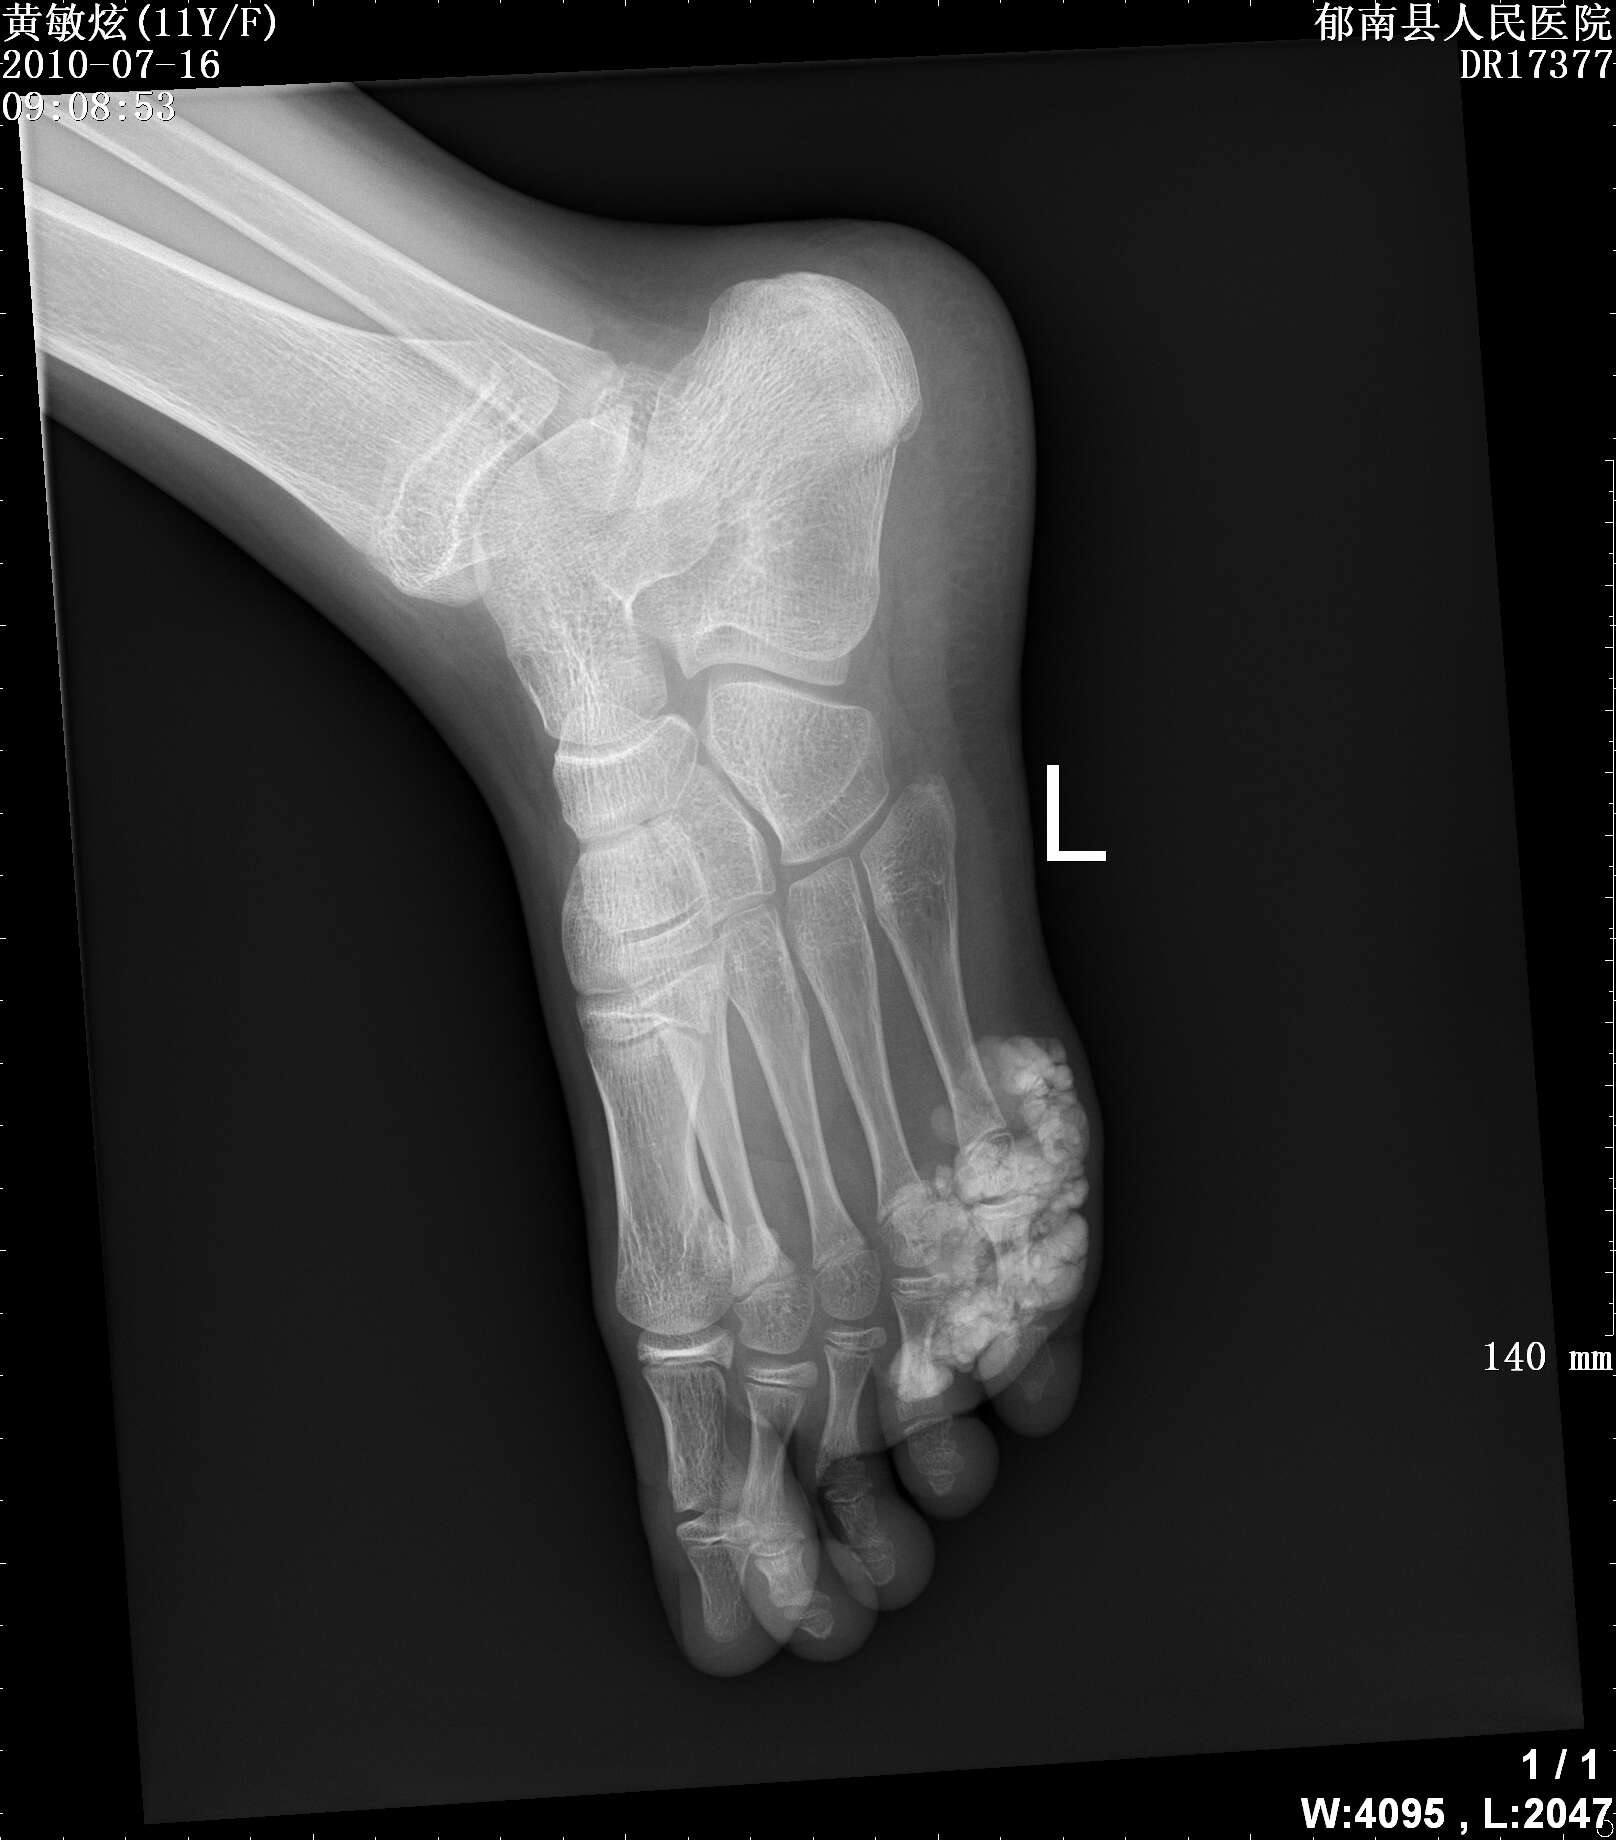

标题: PED3366:女性,11岁,发现左足第五趾肿物2年 [打印本页]

标题: PED3366:女性,11岁,发现左足第五趾肿物2年

女性,11岁,发现左足第五趾肿物2年,压之不痛,质软,无红肿,无外伤史,请各位老师指点下

病理结果是钙化性腱膜纤维瘤,请问各位老师这个病与肿瘤样钙质沉着症怎么区别呢?